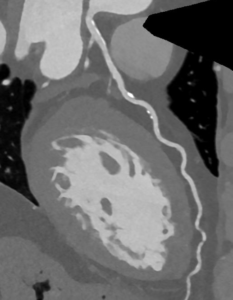

CT coronary angiography (CTCA) is a contrast CT scan that directly images the coronary arteries. It can detect both calcified and non-calcified plaque and determine whether there is narrowing of the vessel lumen. In appropriate patients, CTCA is an excellent test to assess coronary anatomy and can often avoid more invasive testing.

CTCA provides a detailed snapshot of the coronary arteries at a point in time. It is not routinely used for serial monitoring in most people, and treatment decisions are usually guided by symptoms, overall cardiovascular risk, and response to therapy.

In selected patients, advanced analysis of CTCA can provide deeper information about plaque burden and biological risk signals (see CaRi-Heart link). This can help refine preventive strategies beyond what is possible from stenosis assessment alone.

A Photon-Counting CT coronary angiogram reconstruction of the left anterior descending (LAD) artery from the same patient. The lumen and degree of stenosis (narrowing) can be accurately assessed with the aid of contrast dye at high resolution, demonstrating both calcified and non-calcified plaque.